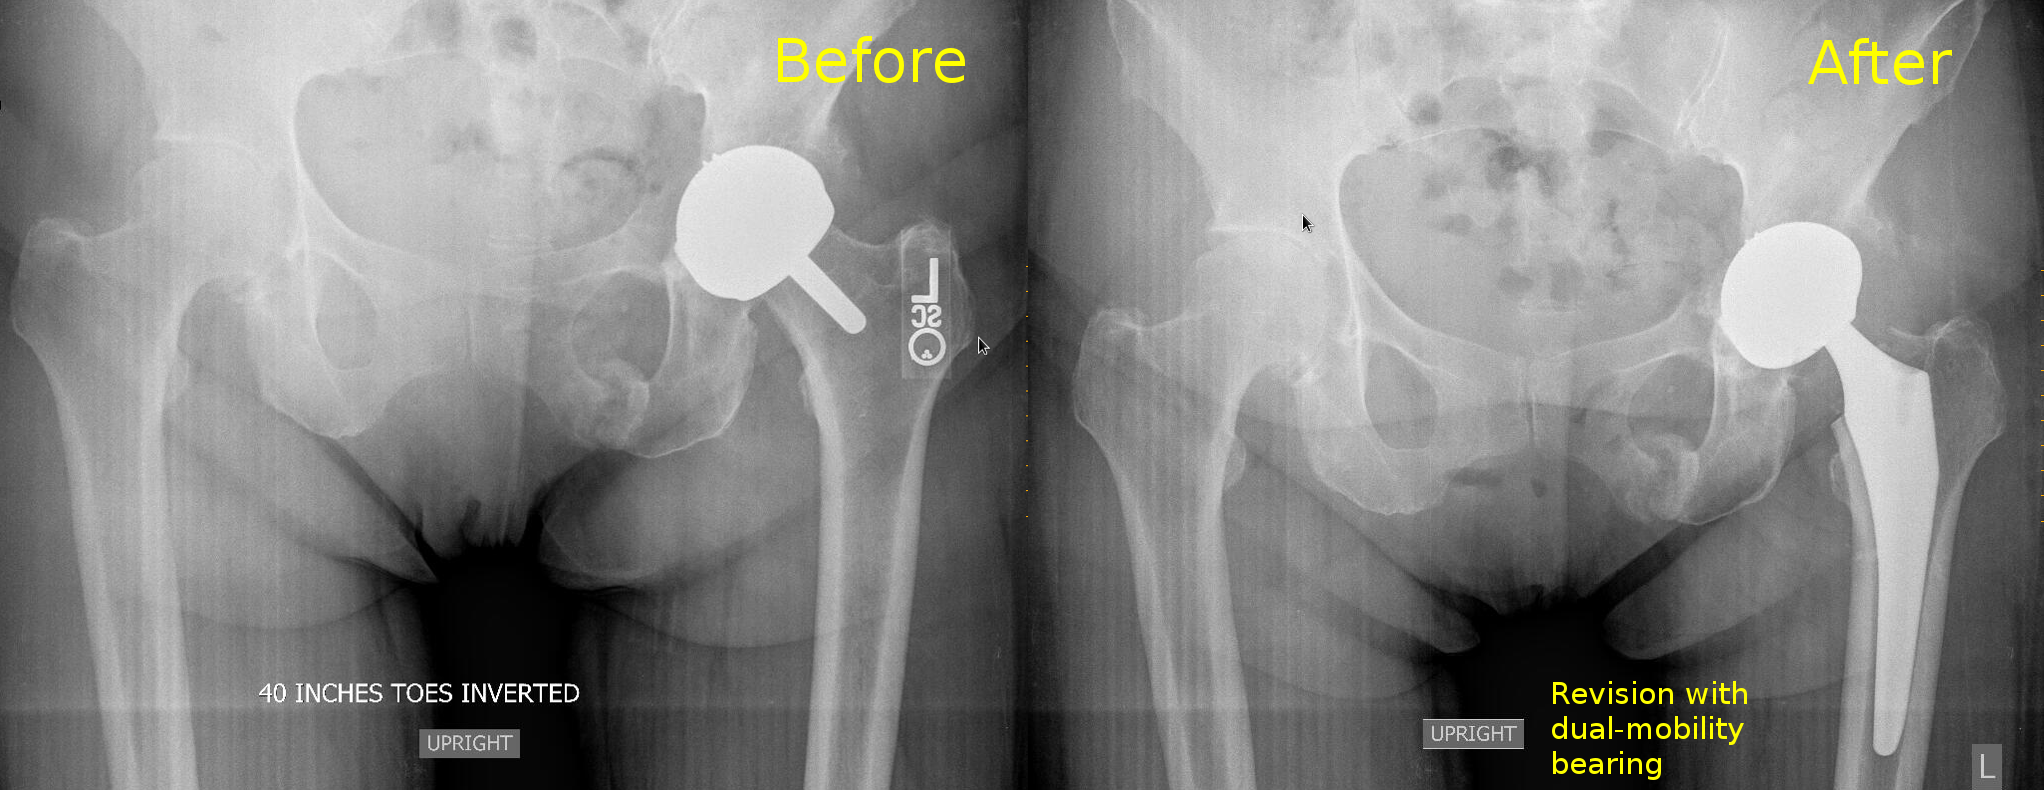

This case is interesting because it is a case of hip resurfacing, the so-called Birmingham hip replacement, which developed a pseudotumor and pubic rami fracture. The pseudotumor can be clearly seen in the xrays, and the blood metal ion levels were very high.

I typically revise the metal-on-metal prosthesis, if possible, by changing the big metal head into a dual mobility bearing. This avoids a femoral osteotomy, and resolves the issue of the metal-on-metal bearing.

For this patient, after revision as above, the metal ion levels came down and the pubic rami fractures healed.